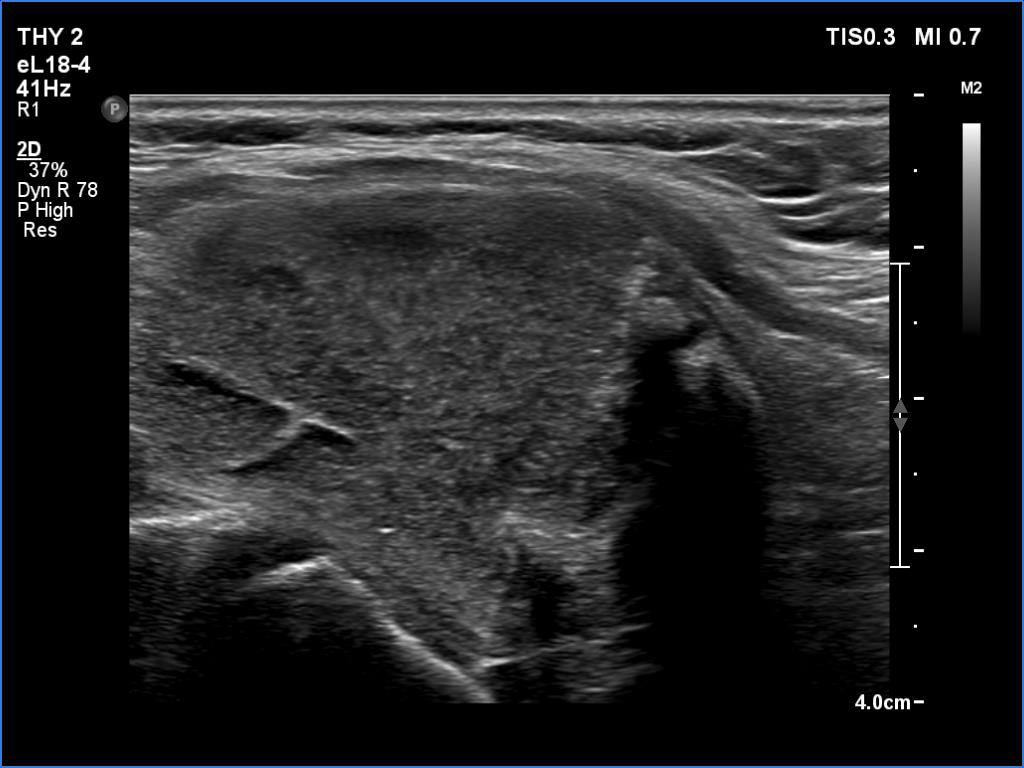

Ultrasonography. The thyroid was echonormal. There were several hypoechoic areas in the right lobe. The left lobe had a large minimally hypoechoic nodule with several tiny cystic areas. The lesion had numerous back wall figures.

In the first part of the ultrasound examination, when the transducer was continuously moving over the thyroid gland, it was not detectable that the contents of the nodule were showing flow. When we stopped the transducer, it became clear that the seemingly solid mass was actually a dense liquid in a continuous flow. On Doppler examination, 'circulation' was visible in continuously changing places.